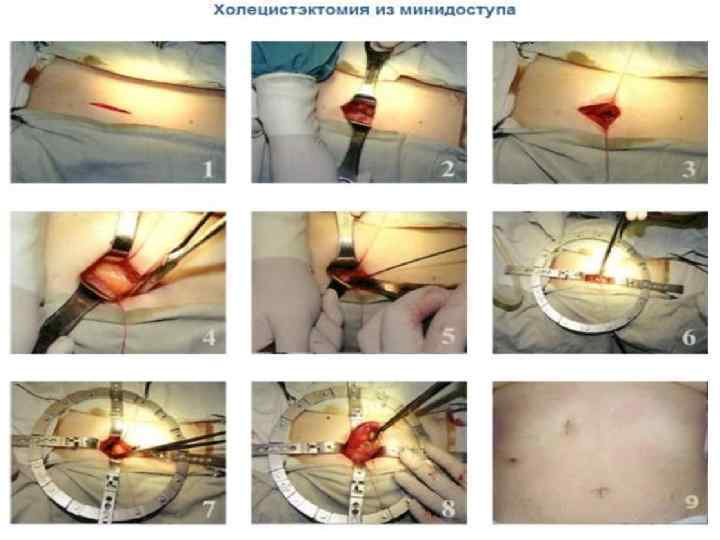

Кіші жолмен жасалатын холецистоэктомия Көрсеткіштері: - жедел калькулезді холецистит - холецистолитиаз, холедохолитиаз, кеңеймеген; -ЛХЭ кезіндегі техникалық қиыншылықтар. Қарсы көрсеткіштер: - іш қуысы ағзаларын интраоперационды ревизия жасау қажеттілігі; - Жайылған перитонит.

Вскрытие брюшины при ХЭ из МПД. Захват дна желчного пузыря окончатым зажимом. Субсерозное выделение желчного пузыря с помощью электрокоагуляции.

Инверсия выделенного на 2/3 желчного пузыря. Схемы дренирования после ХЭ из МПД

"Миниассистент" және "Лига-7 " инструменттерімен